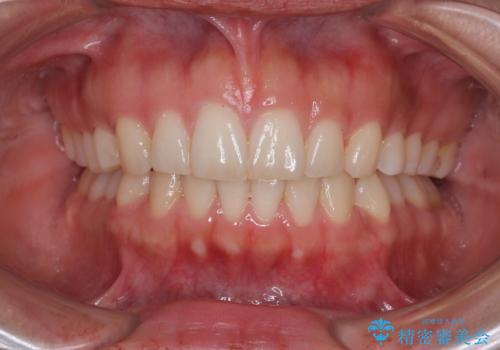

【モニター】突出した前歯 補助装置を併用したインビザライン矯正

- 上下前歯が非接触となり、前方に突出していることを気にして来院された患者様です。

咬合力が強く、全体的に歯がすり減っているため、インビザライン単独での上顎歯列移動は困難と判断し、補助装置により上顎歯列を後方移動させ、その後インビザラインにて仕上げていくこととしました。

補助装置なしでも改善できる可能性はありましたが、補助装置で確実性を上げ、短期間できっちりと仕上げることができました。